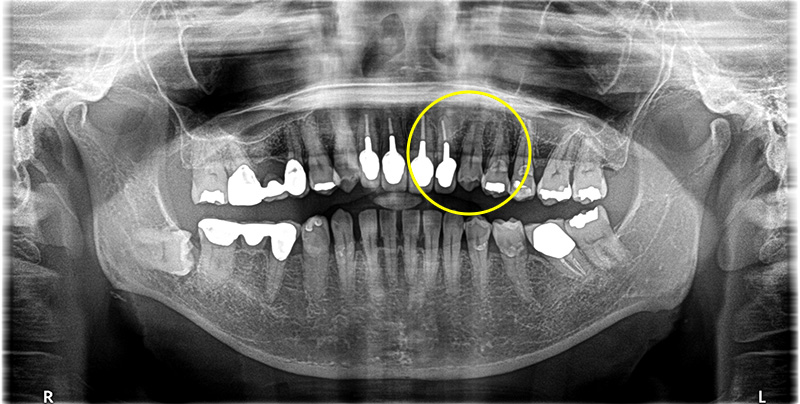

医院全体で1000本以上の実績

安心のインプラント治療

当院では1000本を超えるインプラント治療の実績に基づき、CTによる精密な診断のもと、安全性を優先した治療計画を立案します。 骨造成など難度の高い症例にも対応可能です。 失われた歯の機能と見た目を取り戻すための、良質な方法をご提案します。